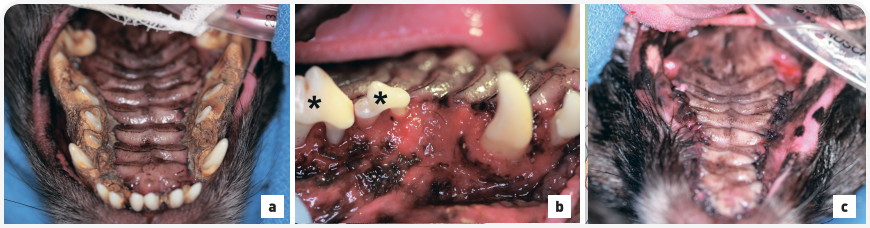

Показания к удалению зуба у собаки вследствие заболеваний пародонта подразумевают клиническую потерю прикрепленности зуба на 50% или выше (по результатам рентгенографии и измерения глубины зубодесневых карманов), обнажение фуркации корней, чрезмерную подвижность зуба. Владелец может быть обеспокоен тем, что собаке требуется удаление всех зубов (Рис. 3). Однако собаки мелких пород обычно довольно хорошо приспосабливаются к их отсутствию. При повторном послеоперационном осмотре владельцы часто отмечают, что собака снова стала активной, веселой, «как щенок».

Рисунок 3.Маленькая собака смешанной породы под общей анестезией в дорсальном лежачем положении для лечения зубов. (a) Обратите внимание на каменный мост на зубах верхней челюсти с заметным гингивитом. (b) В ходе звукового и ультразвукового удаления зубного камня на верхней челюсти выпали первый и второй левые премоляры, первый и второй левые моляры. Обратите внимание на заметный гингивит, потерю альвеолярной кости и обнажение фуркации третьего и четвертого премоляров (звездочки). (c) Пародонтограмма и рентгенография зубов подтвердили необходимость удаления всех зубов; на послеоперационной фотографии показаны лоскуты, закрывающие места удаления зубов, ушитые простым узловым швом с использованием синтетического материала.